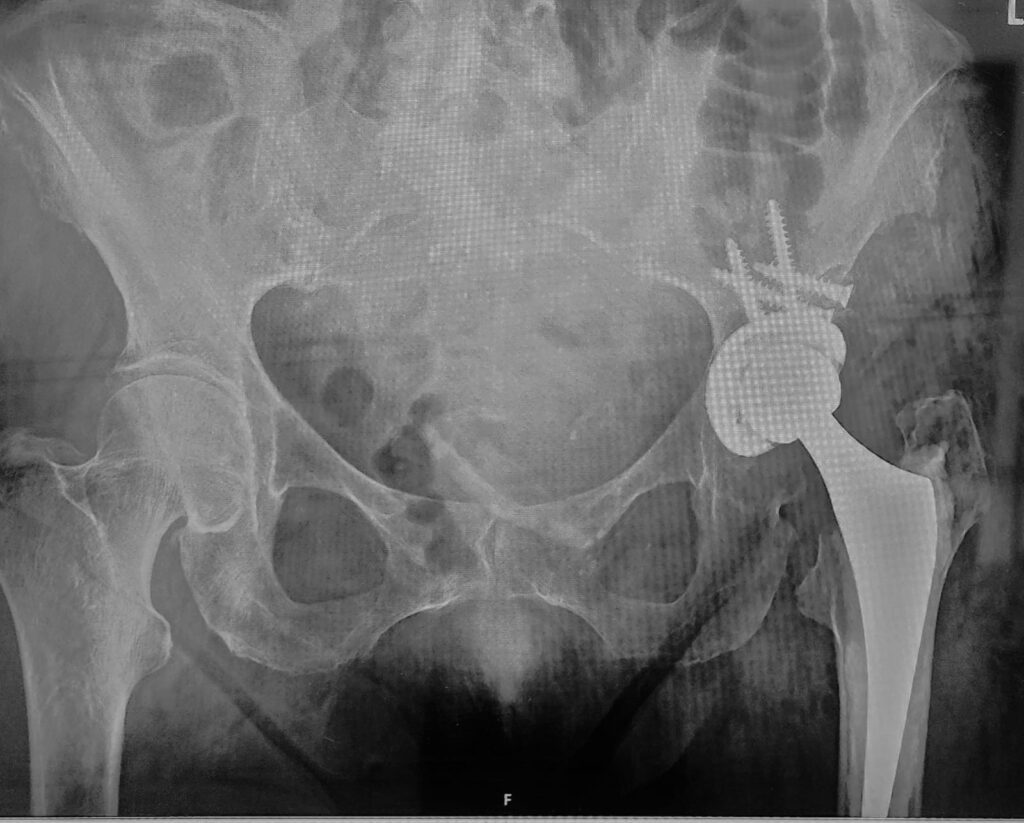

During total hip replacement, the damaged ball of the hip joint is removed and replaced with a metal stem and ball that fit securely into the thigh bone. The shallow socket is reshaped to accommodate an artificial cup, which provides a smooth surface for movement. The goal is to recreate a stable hip center and restore normal joint mechanics.

In patients with hip dysplasia, special implants or techniques may be required to ensure proper fit and long-term stability. Care is taken to balance the muscles and correct leg length without placing excessive tension on nerves. The procedure aims to reduce pain, improve movement, and allow the patient to return to daily activities safely.